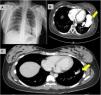

Physical examination was significant for the presence of clubbing and normal vesicular breath sounds. A chest X-ray was performed, revealing an opacity in the left lower lobe (Fig. 1A). No heart valve disease or contractility alterations were seen on echocardiogram. Pulmonary arteriovenous malformation (PAVM) was the principal differential diagnosis, and a shunt was identified after administration of 100% O2 according to protocols, with a calculated shunt fraction of 50%. This was a complex case with a high risk of morbidity and mortality for both the mother and the fetus, so management with the involvement of several hospital departments was discussed by a multidisciplinary committee.

Fig. 1.

Chest X-ray showing an opacity in the left lower lobe. (B) Computed tomography angiography before endovascular embolization. The arrow indicates a large arteriovenous malformation in the left lower lobe. (C) Computed tomography angiography following endovascular embolization with an 18mm Amplatzer. The arrow indicates post-embolization changes in the left lower lobe.

Computed tomography angiography of the thoracic aorta was subsequently performed, in which a left pulmonary arteriovenous shunt was visualized with the presence of a thrombus in its interior (Fig. 1B). The interventional radiology department conducted an embolization of the main trunk of the anterior basal arteries feeding the arteriovenous fistula, using an 18mm Amplatzer via femoral access. Subsequently, two smaller branches were catheterized with 5 and 6mm Amplatzers. The procedure was completed without complications. Radiological monitoring was performed with chest CT after 6 months, showing post-embolization changes in the arteriovenous shunt of the left lower lobe, with no additional alterations (Fig. 1C). The patient currently remains in follow-up with visits to the pulmonology department and shows marked clinical improvement with SatO2 98%.